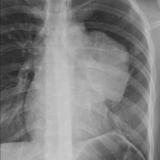

Case 8a Thymoma PA

Date: 03/27/2009

Views: 9454